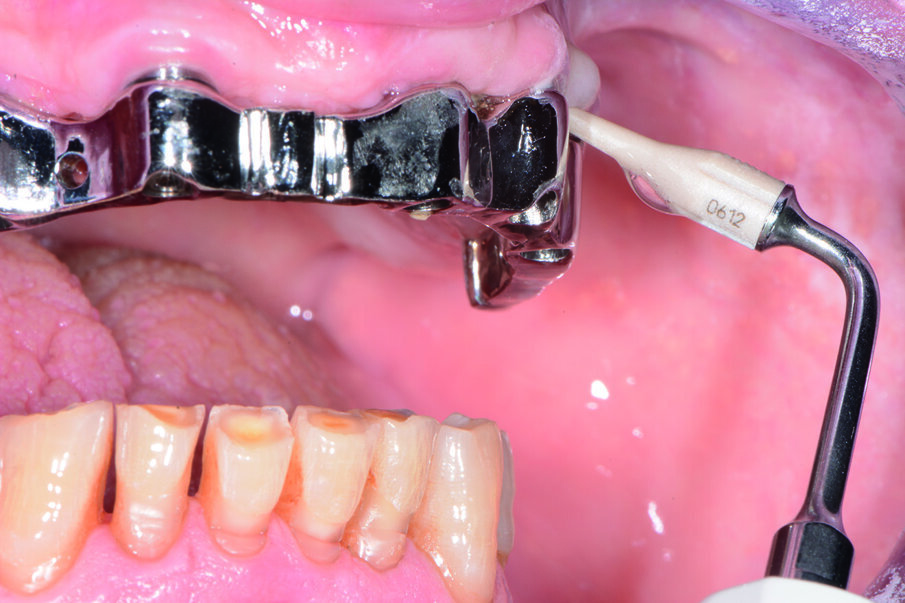

Usiamo airpolishing e polvere di glicina con il sistema di air-polishing Combi-touch (Mectron) in prossimità dei tessuti molli, mentre utilizziamo la polvere di carbonato di calcio Smooth (Mectron) a granulometria tra 45/75 µm a forma sferica con il vantaggio di arrivare nei siti ritentivi di biofilm batterico più adeso come a esempio per le zone interprossimali e per i margini gengivali (Fig. 14). Questa nuova tecnologia di polvere dà l’opportunità di lasciare le superfici trattate con un effetto brillante e non richiede il polishing successivo. Eseguiamo il debridement con il Combi-touch e la punta S1S e la punta in Peek (Fig. 15) ideale per i manufatti implantari. Il vantaggio ergonomico di eseguire il debridment con un ablatore multifunzionale piezoelettrico e un air-polisher con l’uso di polveri di carbonato di calcio e glicina sopra e sottogengivale permette una operatività clinica più agevole e meno fastidiosa per il paziente. L’opportunità di poter usare i manipoli orientati a 90° o 120° permette di poter essere efficaci nel rispetto della delicatezza dei tessuti e del manufatto implantare, erogando il getto in maniera personalizzata e mirata, con un’operatività clinica minimamente invasiva.

Usando la polvere “perio” non si corrono rischi di danneggiare né il manufatto protesico né il collo dell’impianto, unendo a queste caratteristiche anche la praticità d’uso e la velocità di esecuzione, potendo tranquillamente dirigere il getto sia sulla protesi sia sull’impianto, senza limitazione di inclinazione del fascio erogato e senza rischio alcuno per entrambe le strutture. Solo successivamente al deplaquing, si procede con il sondaggio, evitando così la trasmigrazione batterica, con una sonda implantare in materiale plastico Wingrove™ (PDT). La polvere di glicina si è dimostrata una vera e propria rivelazione nel trattamento delle mucositi e perimplantiti. Dopo la detartrasi dalla superficie esposta degli impianti, effettuabile con i metodi classici (curettes in teflon o titanio) o utilizzando punte a ultrasuoni specifiche, un’ulteriore detossificazione della superficie degli impianti con il perio-polishing garantisce – in 8 casi su 10 – la completa guarigione della patologia (Sarri et al., 2006) per tasche non superiori a 5 mm. Nel caso non ci fosse tartaro sul titanio del collo implantare, ma l’infiammazione fosse indotta da placca batterica, l’utilizzo del perio-polishing è efficace per migliorare la guarigione del sito attivo.